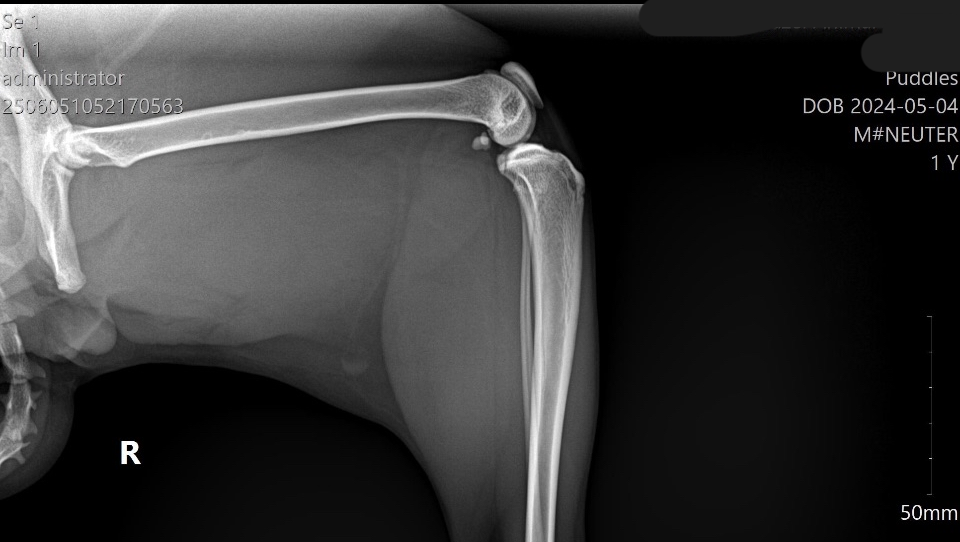

Xrays ⬇️

We rushed him to the vet the next day. That alone cost nearly $700, which completely drained us. They did X-rays and gave him pain meds, and the next day we got the news: Puddles has a fractured femur near the hip, and he needs a surgery called an FHO (femoral head ostectomy) to be able to walk normally again without pain.